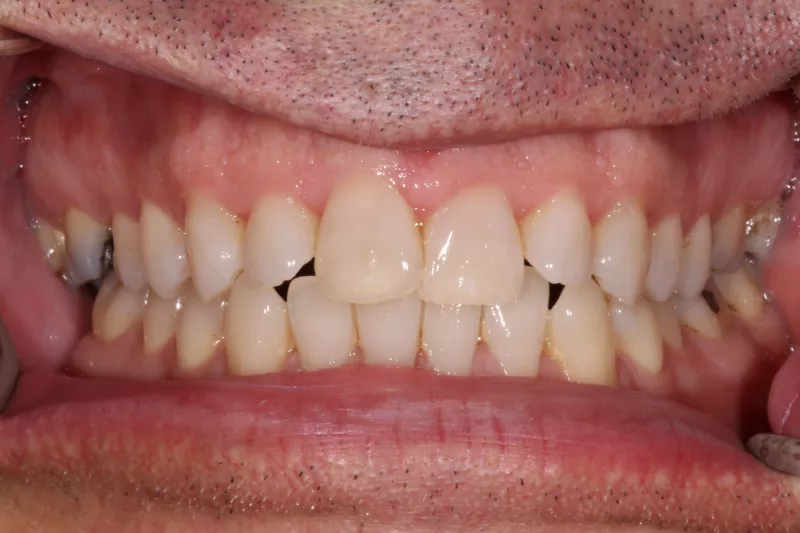

Clear Dual Arch Aligners. Overcrowding and gaps were fixed in under 6 months